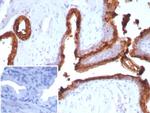

Prostate Specific Acid Phosphatase (PSAP) Antibody in Immunohistochemistry (Paraffin) (IHC (P))

Formalin-fixed, paraffin-embedded human prostate carcinoma stained with PSAP Mouse Recombinant Monoclonal Antibody (ACPP/2472). HIER: Tris/EDTA, pH9.0, 45 min. 2°C: HRP-polymer, 30 min. DAB, 5 min. {{ $ctrl.currentElement.advancedVerification.fullName }} 验证信息 View more